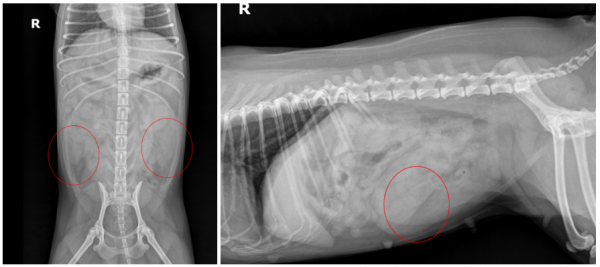

먼저 방사선 검사(X-ray)에서

➡ 복강 내에 연부조직 밀도의 원통형 구조물이 확인되었으며,

확장된 자궁으로 의심되는 소견이었습니다.